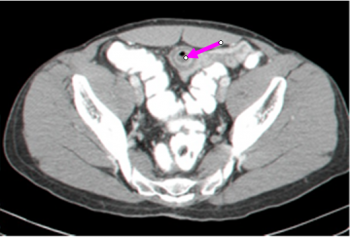

ברוב החולים האבחנה היא מקרית, והיא לרוב נעשית בזמן פתיחת הבטן מסיבות אחרות. בחלק מהחולים הסעיף נראה ב- CT (תצלום 20.4) בחולים תסמיניים או א-תסמיניים. בחלק אחר של החולים אפשר להדגים את הסעיף במיפוי. נדיר אולם ניתן למצוא את הסעיף בזמן ניתוח בקע - בקע על שם Littre.